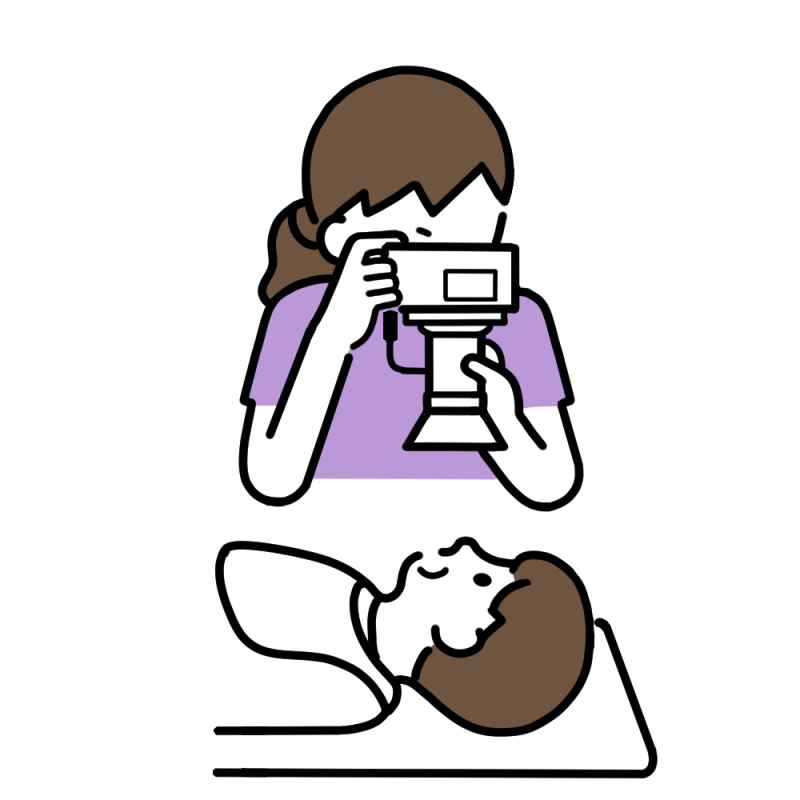

精密検査

カウンセリング後、矯正治療を始める前に必ず行うのが精密検査です。現在のお口の状態を把握し、今後の治療方針を決めるうえで非常に重要となります。

精密検査は主に4つの項目にわかれており、それぞれが適切な矯正治療を行うための診断に非常に重要な項目となります。詳しくは下記ブログをご覧ください。